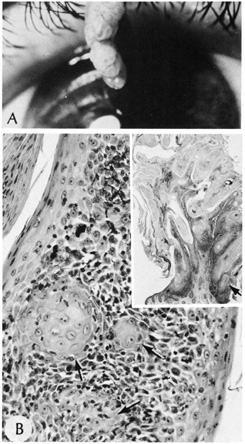

Umbilicated vesicles on an erythematous base progressing to pustules and crusted papules are characteristic of generalized vaccinia (small pox), with new cases recently reported secondary to the small pox vaccine. These vesicles are also characteristic of varicella (chickenpox), herpes zoster (shingles), and primary and recurrent herpes simplex infections (Fig. 6A). Herpesviruses are DNA-containing viruses that infect host cell nuclei resulting in similar, characteristic histologic changes. There is marked intraepidermal vesiculation and necrosis with massive ballooning and rupture of keratinocytes, spongiosis, acantholysis, and a dense superficial dermal perivascular lymphohistiocytic infiltrate with neutrophils, which also are seen commonly infiltrating the epidermis. Multinucleated epithelial giant cells with nuclei, which are steel gray and demonstrate peripheral margination of clumped chromatin material, are characteristic of early and well-developed vesicles (see Fig. 6B). Progression to near total epidermal necrosis makes these characteristic cells more difficult to identify. Occasionally, eosinophilic staining and small intranuclear inclusions may be visible. A Tzanck smear may be obtained by unroofing a vesicle, scraping the base, and staining the base with Giemsa stain. This rapid diagnostic method enables identification of multinucleated epithelial giant cells and single keratinocytes with characteristic nuclear changes.

Fig. 6. A. Recurrent herpes simplex infection with umbilicated pustulovesicles on an erythematous base. B. Herpes simplex infection with intraepidermal vesicle containing characteristic multinucleated epithelial giant cells.